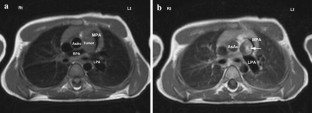

Fibroma, the second most common tumor in childhood, usually is a large solitary mass involving the ventricular septum or the left and rarely the right free ventricular wall. An unusual case of a 5.2-year-old boy with a large mass originating from the pulmonary valve is reported. The patient presented for evaluation of a murmur. Echocardiography and cardiac magnetic resonance imaging showed a large tumor extending from the distal right ventricular outflow tract through the pulmonary valve and into the main pulmonary artery causing moderate obstruction. The patient had a fatal cardiac arrest while awaiting surgery. The postmortem examination proved the tumor to be a fibroma.

Fig. 3